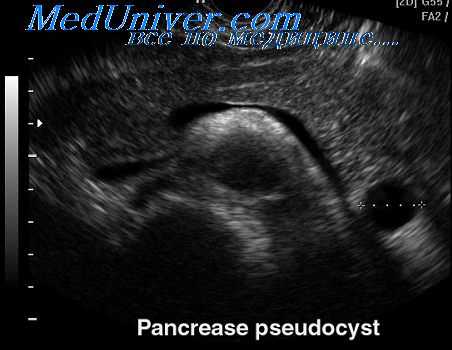

Наружное дренирование псевдокисты поджелудочной железы

Наружное дренирование псевдокисты поджелудочной железы показано, когда киста быстро растет и существует угроза ее прорыва в брюшную полость. До тех пор пока стенка кисты не созрела, ее невозможно анастомозировать с пищеварительным трактом. Для наружного дренирования кисты производят срединный разрез между мечевидным отростком и пупком. Содержимое кисты аспирируют шприцем с иглой № 16. Производят бактериологическое и цитологическое исследование жидкости, определяют уровень ферментов.

Псевдокисты, которые увеличиваются до опасного размера, можно также пунктировать чрескожным доступом под контролем УЗИ или компьютерной томографии. Чрескожное дренирование должно выполняться в учреждениях, имеющих достаточный опыт проведения таких процедур. Показано, что у больных, которым выполнено чрескожное дренирование псевдокист, рецидивы возникают значительно чаще, чем у тех, которым выполнена хирургическая операция.